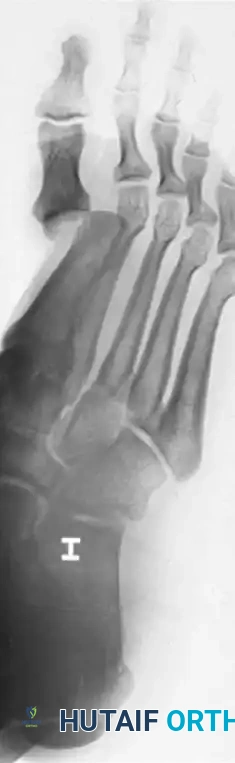

Radiographic Assessment

Standard weight-bearing (if tolerated) anteroposterior (AP), lateral, and oblique radiographs of the foot are mandatory. The lateral view will clearly demonstrate the dorsal displacement of the proximal phalanx. The AP view is critical for assessing the sesamoid complex to apply the Jahss classification.

Radiographic examples demonstrating complex dislocation patterns of the first ray. Note the displacement of the sesamoid complex which dictates the Jahss classification and subsequent reducibility.